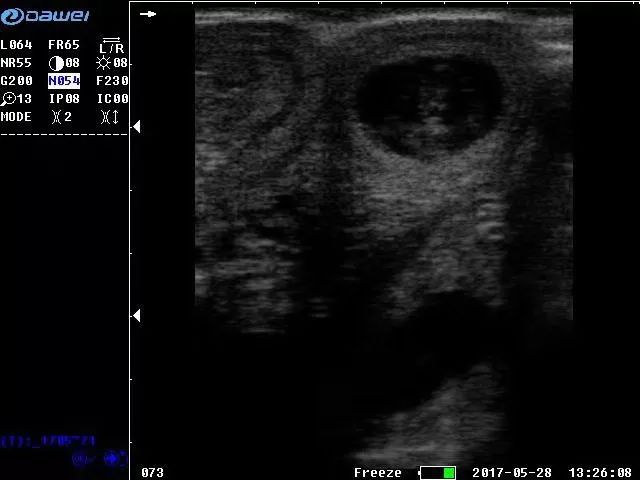

在使用獸用b超機對寵物進行檢測時,想要獲得優質的b超圖像,除了需要熟悉寵物身體組織的構造外,對于b超機本身的按鍵與功能也要非常熟悉。同樣的一款的寵物獸用b超機,參數設置如果不一樣,就會得到不一樣的b超效果圖,那么如果想獲得良好的b超圖像,獸用b超機怎么調節?既然是以獲得優質的b超圖像為目的,那我們首先要搞清楚,影響b超圖像質量的參數有哪些,了解了以后,我們可以有針對性的去調節,從而提高我們b超檢測時的圖像質量。

單從理論上來說,影響獸用b超機圖像質量的因素有很多,如頻率,增益,諧波,幀相關,動態范圍,線密度等等,但是影響較大,較為主要的,主要有以下幾個方面:

1、獸用b超的探頭頻率選擇

獸用超聲的探頭頻率有高有低,超聲頻率越高,其顯現力和分辨力就越強,顯示的組織結構或病理結構就越清晰。但是并不是頻率越高就越好,在對寵物進行b超檢測時,不同部位對于頻率的要求不一樣,有高有低。頻率越高,其衰減也越顯著,透入的深度就會大為下降。

探頭頻率的選擇應遵循以下原則:

●淺表的部位觀察目標深度<6cm

探頭的頻率7.5MHz- 10MHz

比如小型犬、幼犬、  貓

●較深的部位觀察目標深度6cm以上

中低頻探頭的頻率3.5MHz-6.5MHz

比如大、中型犬

獸用b超機成像圖

獸用b超機圖像